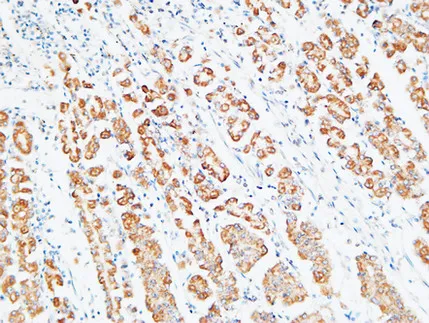

Na+/K+-ATPase α1 Rabbit Polyclonal Antibody

Cat: APRab14378

Size1:50μl Price1:$118

Size2:100μl Price2:$220

Size3:500μl Price3:$980

Size2:100μl Price2:$220

Size3:500μl Price3:$980